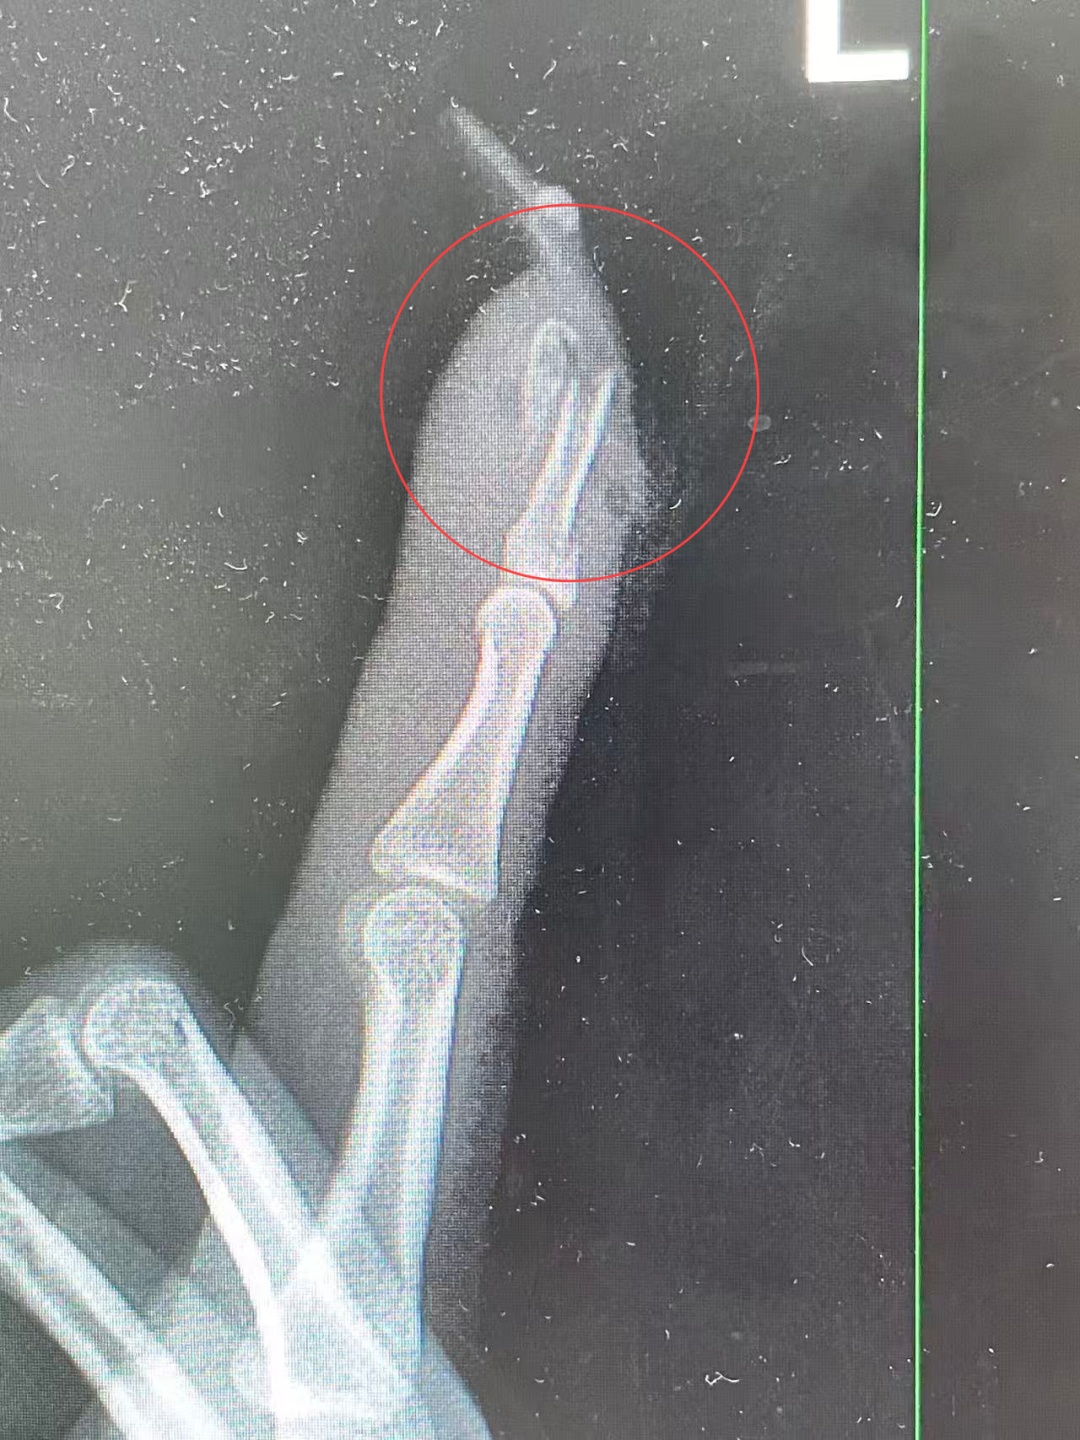

“左手食指指骨骨折,甲床破裂,部分甲床外露,需要手术修复。”接诊的曹立副主任医师检查后作出诊断,并当即对其做了指骨骨折闭合复位内固定术。

王小姐术前的X光影像